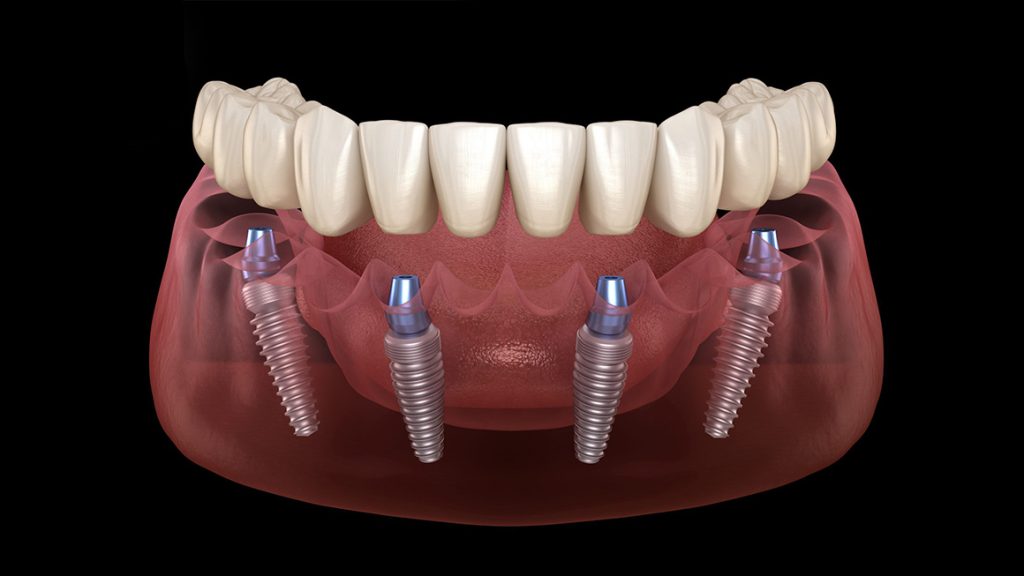

Modern diş hekimliğinde en çok tercih edilen sabit protez çözümlerinden biri olan All On Four İmplantlar, tamamen dişsiz veya ileri derecede diş kaybı yaşayan hastalar için geliştirilmiş yenilikçi bir sistemdir. Bu teknikte üst veya alt çeneye yalnızca dört adet implant yerleştirilir ve bu implantların üzerine tam ark sabit protez uygulanır. Böylece All On Four İmplantlar, hem hızlı hem de fonksiyonel bir şekilde yeni bir gülüş kazandıran ideal bir tedavi yöntemi sunar.

Diş protez laboratuvarlarında ve kliniklerde kullanılan All On Four İmplantlar, materyal ve üst yapı tasarımına göre çeşitlenebilir:

Daha ekonomik bir çözüm sunar ve işlem sonrası hızlı şekilde hazırlanabilir.

Dayanıklılık ve estetiği bir arada sunduğu için en çok tercih edilen premium seçenektir.

Titanyum altyapı ve kompozit kaplama ile hem sağlam hem de estetik bir yapı sağlar.